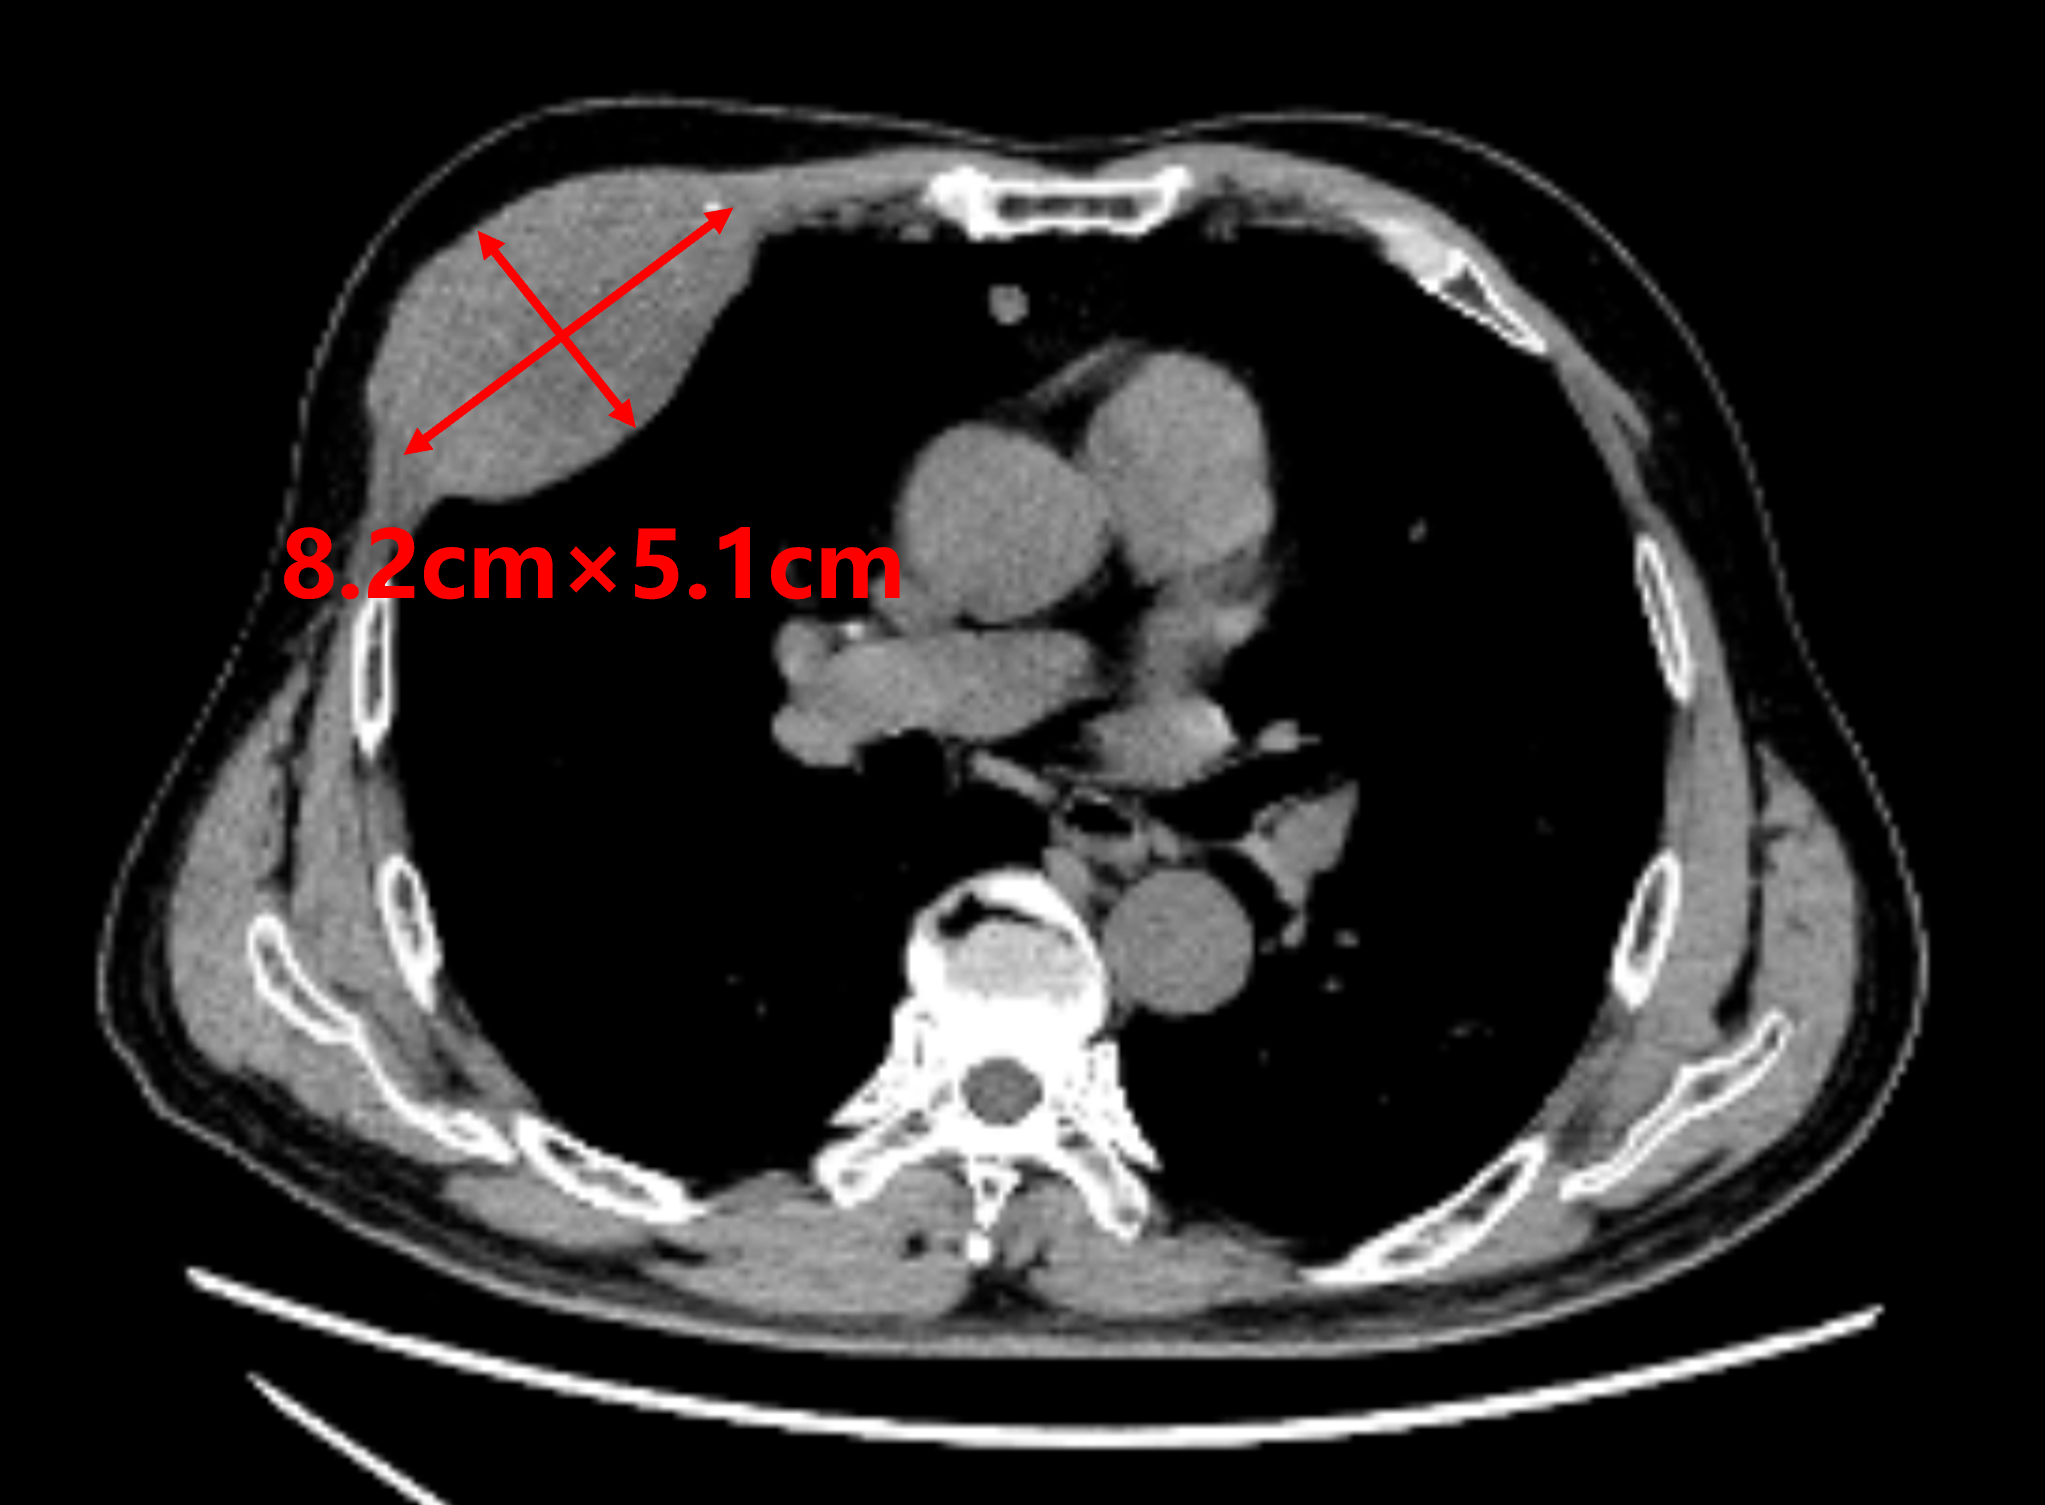

患者1年前罹患原发性肝癌,经多学科综合治疗后肝内肿瘤控制稳定,但近期出现右胸壁局部疼痛不适,严重影响睡眠等日常生活。进一步检查发现右第4前肋骨骨质破坏伴软组织肿块形成,大小约8.2cm×5.1cm,提示为肝癌右胸壁转移。

针对此类位于胸壁的局限性转移病灶,碘125放射性粒子植入是一种有效的局部内放射治疗手段。鉴于该患者胸壁病灶范围大,为达到理想的治疗疗效及最小的副反应,需通过多针道、高空间一致性穿刺操作技术才能实现碘125粒子剂量辐射的高度适型,而传统CT引导穿刺方式无法确保实现最优剂量分布与高效率操作。